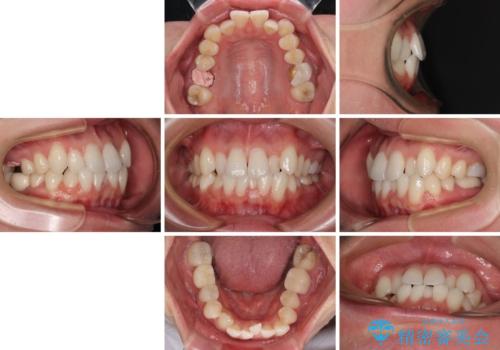

ワーキングホリデー前にきれいな歯列に

- 2、3年後にワーキングホリデーで海外に行くため、その前に歯列やむし歯をきれいにしたいとのことで来院された患者様です。

抜歯の必要な右上の奥歯は事前に抜歯をし、インビザラインにて上下歯列を整えることとしました。

矯正治療後半に奥歯の補綴治療が必要な歯にはオールセラミッククラウンを装着し、インビザラインで最終的に仕上げることとしました。